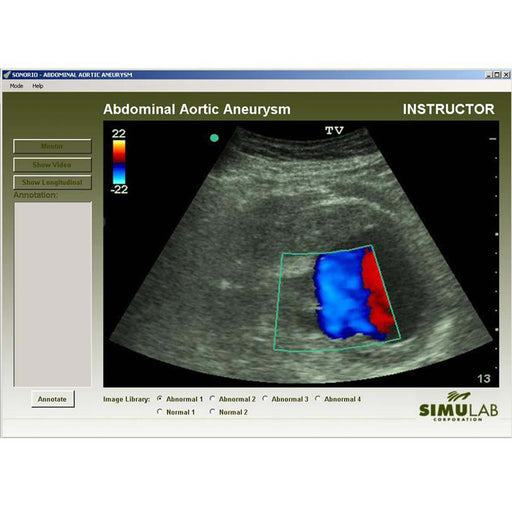

The training system offers an extensive image and video library with an option of six software modules (sold separately). Each module provides up to seven clinical cases presenting normal or abnormal findings, allowing the instructors to mimic various pathologies in emergent or critical care settings.

Within the software modules, instructors can pre-program pathologies allowing users to assess, locate, and then diagnose the patient while visualizing the complete thoracic and abdominal region.

- Images and videos are of actual patients - both normal and abnormal

- Each module includes an instructor (enable visual instruction with mentor mode to discuss pathology and diagnoses) and student mode (randomly selects patient to build diagnosis and decision-making skills)

- Mentor mode allows users to activate onscreen guidance identifying the anatomy and pathology of digital images

- Understand and diagnose disease states using patient images, videos, and ultrasound acquisition on the body form